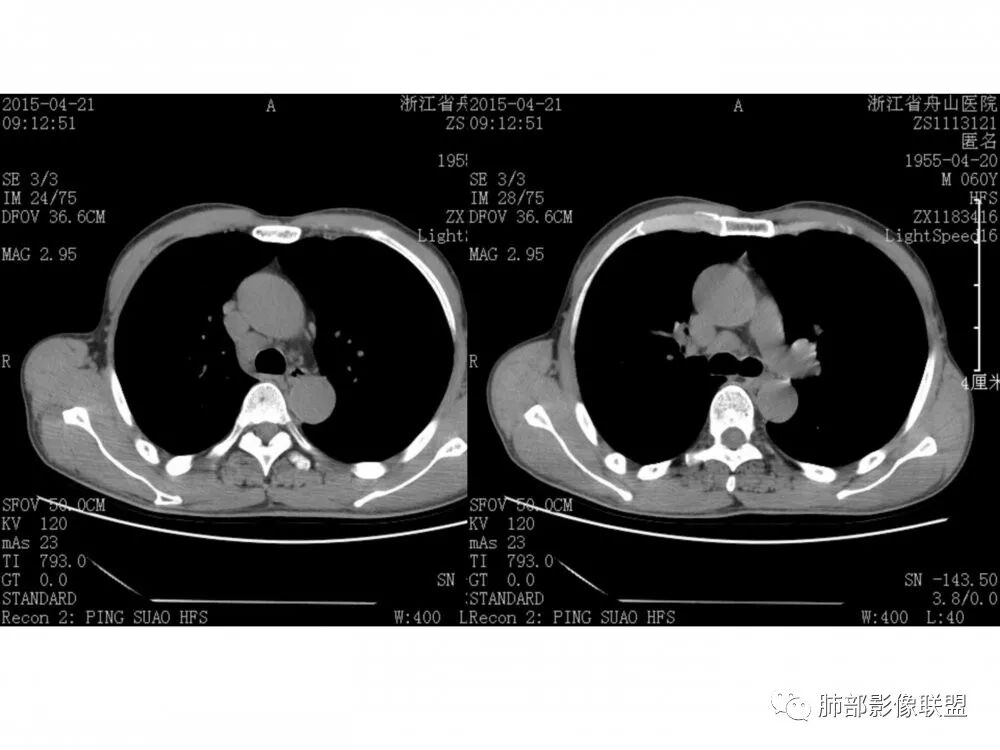

右肺下叶支气管开口新生物,轴位管腔及纵向基底干大部分受累狭窄,支气管管壁破坏明显,强化较低不均匀,肺门、7组、4R淋巴结肿大,考虑恶性支气管腔内肿瘤,鳞癌可能性大,需要与类癌、涎腺类肿瘤鉴别

老年男性,60岁,右下肺门肿块,右下支气管粘膜下生长,并堵塞,无明显阻塞性肺炎和肺不张,早期多发淋巴结转移,似不均匀强化。综合看恶性程度高,考虑大细胞癌,一个不支持点,大细胞癌外周多见。

优先需要与小细胞癌鉴别,再鳞癌鉴别。肿瘤恶性程度排序,小大腺鳞类。小细胞癌不支持点是:1.沿着支气管粘膜下生长,支气管阻塞轻,爬行征;2.包绕血管,冰冻纵隔,有可能病灶比较小,所以没那么快包裹;这例这点不符合。其他倒是符合中央型小细胞癌,比如转移早,恶性程度高。

男,60岁,右肺下叶支气管开口新生物,轴位管腔及纵向基底干大部分受累狭窄,支气管管壁破坏并突破形成腔外肿块,强化较低不均匀,右肺门、7组、4R淋巴结肿大,考虑恶性没问题,鳞癌可能性大,类癌、粘液表皮样癌,乳头状瘤待排。